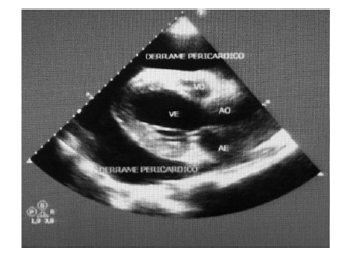

Considere um paciente de 58 anos de idade, etilista, com hipertensão arterial e doença renal crônica. Apresenta irregularidade nas sessões de terapia renal substitutiva e comparece a consulta médica com histórico de batedeira, ortopneia, PA = 89 mmHg x 43 mmHg; FC = 126 bpm; SatO2 = 95% (ar ambiente), FR = 26 ipm, ausculta pulmonar limpa e ausculta cardíaca quase inaudível. Encaminhado para sala de ecofluxo, retorna com o ecocardiograma mostrado: dilatação acentuada do átrio esquerdo e moderada do VE; hipertrofia excêntrica do VE; função sistólica do VE deprimida em grau moderado; hipocinesia difusa do VE; insuficiência mitral discreta; e derrame pericárdico de grau acentuado com sinais ecocardiográficos de aumento das pressões intrapericárdicas – sinal de “swimming heart”.

Nesse paciente com instabilidade hemodinâmica, é correto esperar um pulso paradoxal.Comentários